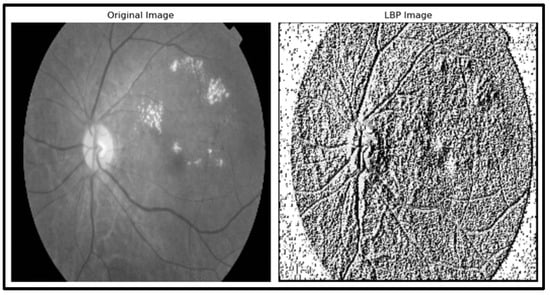

- LBP